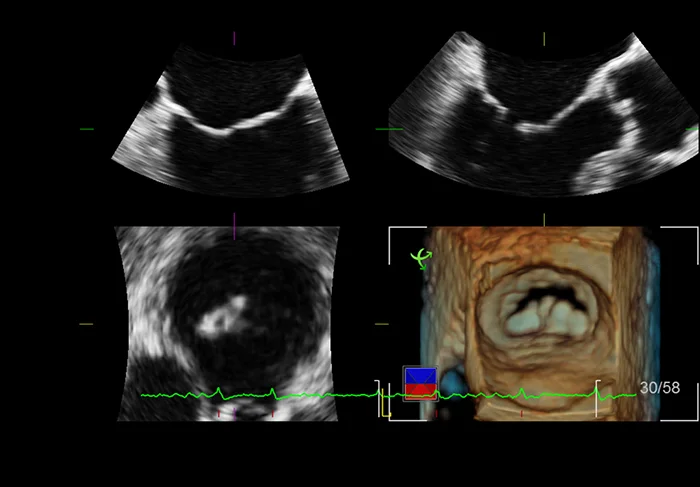

Объёмная эхокардиография

Трёхмерная реконструкция в эхокардиографии обеспечивает более наглядное и точное отображение морфологии сердца. Такое сканирование позволяет не только досконально оценить патологию, но также предоставляет критическую информацию, необходимую для планирования, проведения и оценки эффекта лечения.

Специальная программа производит трёхмерную реконструкцию потоков крови в камере сердца. К примеру, благодаря этому, возможно оценить истинный размер потока регургитации во всём объёме области интереса.

С помощью кардиологического матричного датчика осуществляется одновременный вывод двух плоскостей сканирования в реальном времени, в том числе с цветовым допплеровским картированием кровотока. Доступны поворот или наклон плоскостей друг относительно друга. Такая функция значительно ускоряет процедуру исследования и повышает его наглядность.